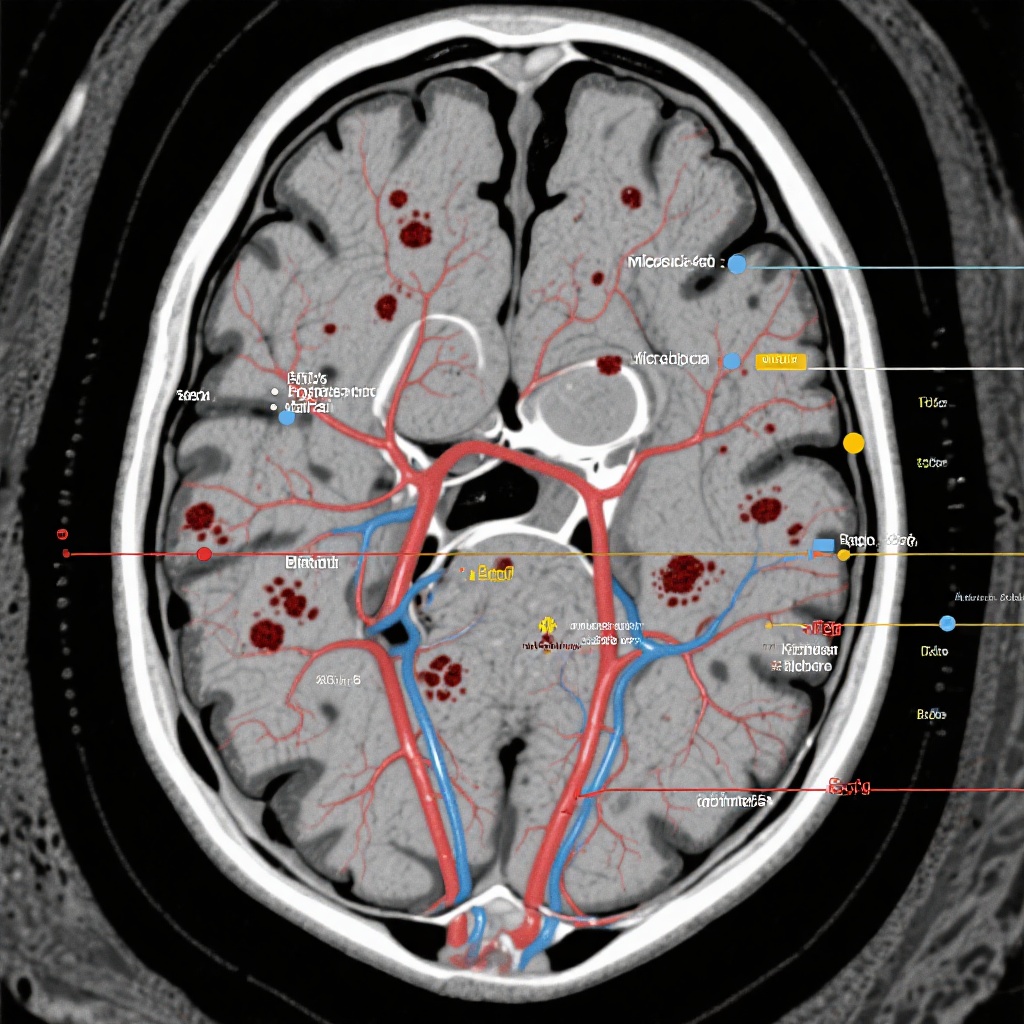

主要发现:出血事件的比较分析

分析包括完成基线和随访MRI扫描的174名患者(阿哌沙班组79名,阿司匹林组95名)。基线时,两组治疗队列的人口统计学特征和既往MRI标志物的患病率平衡良好,为比较随访期间新病变的发生率提供了稳定的基线。

新发出血事件

结果显示,阿哌沙班组与阿司匹林组在新发出血性病变的发展方面没有统计学显著差异。具体发现如下:

1. 颅内出血(>10毫米)

阿哌沙班组中有5.1%的患者发生新发ICH,而阿司匹林组为6.4%。尽管数值上稍有利于阿哌沙班,但差异未达到统计学显著性(P > 0.05)。

2. 脑微出血(≤10毫米)

阿哌沙班组中有7.8%的患者出现新发微出血,而阿司匹林组为10.8%。再次证明,使用阿哌沙班抗凝并未导致小血管出血标志物的负担高于标准抗血小板治疗。

3. 皮层浅表铁沉积症(CSS)

阿哌沙班组中有7.7%的患者出现新发CSS,而阿司匹林组为12.9%。这一发现尤其值得注意,因为CSS是未来症状性ICH的强预测因子,而阿哌沙班组未见增加支持其安全性。

总体而言,探索性分析表明,与阿司匹林相比,阿哌沙班在这一特定高危卒中人群中与放射学出血标志物的风险增加无关。